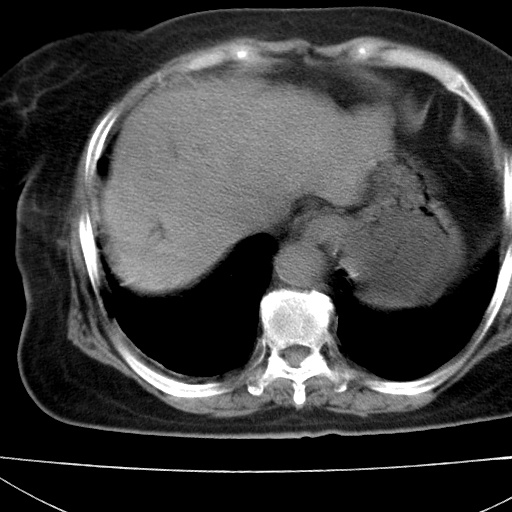

患者女74岁;右上腹胀痛1月,伴恶心,无发热;生活在疫水区。有术后病理及术后半年的追踪ct.

1)慢性血吸虫病(典型)。2)肝硬化。3)肝癌?4)胆囊炎。5)少量腹水。6)右侧少量胸腔积液。

肝脏体积缩小,肝裂增宽,边缘不平呈波浪状,肝右叶见分隔状条索形钙化,亦见多结节低密度灶,边界不清,肝周可见少许液性暗区,胆囊增大内密度均匀,脾脏下缘低于脏脏的下缘,胸腔亦见液性暗区,余未见明显异常.

诊断:1肝硬化并慢性吸血虫病,脾肿大

2肝内占位,考虑肝癌可能性大,建议做增强

3胆囊炎, 4少量腹水及胸水

胆囊增大饱满,壁增厚。胆囊颈部见软组织密度影。临近肝右叶前段见片状低密度区,病灶下部见条状钙化,少量胸腹腔积液。意见:胆囊颈癌累及肝脏。

病人以胆囊癌手术的,病理结果为中分化腺癌。

现在看看肝右叶内圆形低密度影你们考虑什么呢?

肝内圆形低密度影考虑扩张的胆管

请看3mm重建像如下: